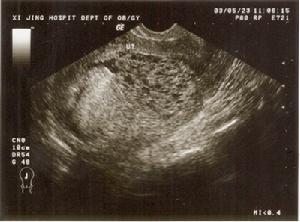

3.超聲檢查

正常妊娠在孕4~5周時,可顯示妊娠囊,孕6~7周可見心管搏動,最早在孕6周時即可探測到胎心,孕12周后均可聽到胎心。葡萄胎時宮腔內呈粗點狀或落雪狀圖像,無妊娠囊可見,亦無胎兒結構及胎心搏動征,只能聽到子宮血流雜音,聽不到胎心。